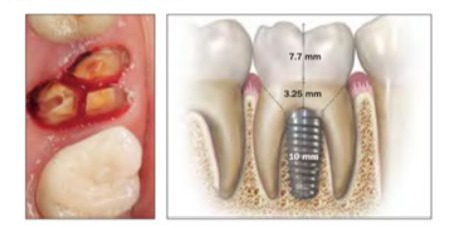

In the original report, molar extraction sockets were divided into three classes (Figure 1a-c) [4]. A type A socket has sufficient septal bone to cover the coronal portion of the implant completely inside the bone. A type B socket has enough septal bone to secure the implant but not fully cover it. A type C socket does not have enough septal bone inside the socket, but a Wide Diameter Implant (WDI) can be stabilized with engagement of the peripheral bone walls of the socket (Figure 1c). Two more classes, type D socket and type E socket, are introduced. A type D socket does not allow implant stability with a WDI, which cannot be engaged in the outer wide periphery wall, has little to no septal bone, but has just one of the root sockets and buccal bone remains (Figure 1d). A type E socket does not allow implant stability with a WDI for the same reasons, and there is neither septal bone nor any root socket, but buccal bone remains (Figure 1e). The cases of Type D and Type E sockets experienced by the authors are shown in (Table 1). Surgery was performed by two surgeons who shared the same protocols.

Figures. 1(a-e): a. A type A socket. An implant to fit completely for stability within the septal bone.

- A type B socket. An implant to fit for stability within the septal bone but to cover with bone incompletely.

- A type C socket. A WDI can be fixed within the socket wall and/or apical bone because no or incompletely septal bone for stability.